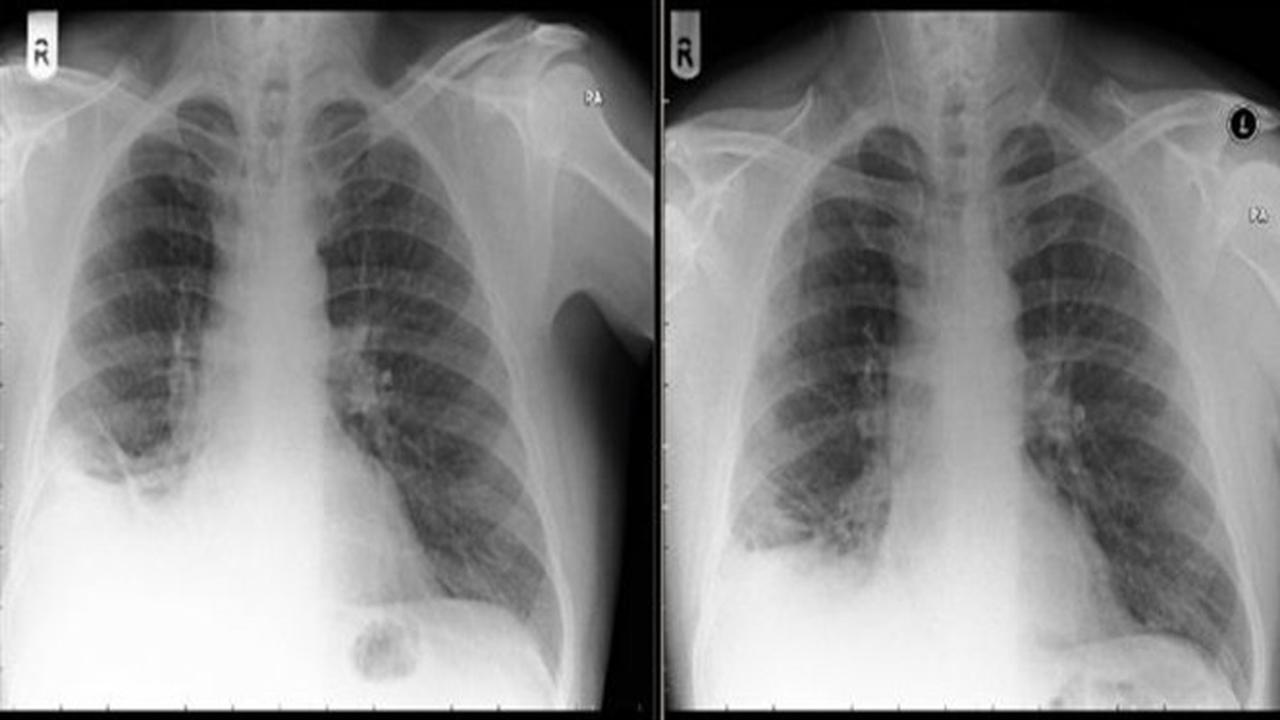

Setelah melakukan pemeriksaan lewat sinar X, dokter mendiagnosis Paul dengan tumor ganas, karena dari hasil pemeriksaan tampak sebuah benda menyerupai tumor di paru-paru sebelah kanan.

Diagnosis itu tak lama berubah, saat dokter kembali melakukan pengecekan menggunakan bronchoscopy, prosedur yang memungkinkan dokter melihat saluran pernapasan pasien menggunakan alat bronchoscope.

Dokter di Royal Preston Hospital, menemukan, ada miniatur traffic cone berukuran kecil bersarang di paru-paru Paul.

Akan tetapi, dalam banyak kasus, dokter dapat mendiagnosisnya dalam waktu seminggu. Berbeda dengan Paul, yang kini berusia 50 tahun, miniatur yang sangat kecil itu justru bersarang di paru-parunya selama 40 tahun.

Adanya miniatur traffic cone di dalam paru-paru Paul membuat ia mengalami batuk terus-menerus. Setelah mainan itu dikeluarkan dari paru-parunya, empat bulan kemudian, batuk pun sembuh.

"Kesembuhan ini sebagai pertanda, kesehatan ia membaik. Akhirnya, pertanyaan dia terjawab. Miniatur traffic cone yang telah lama hilang tertelan ke paru-parunya," menurut keterangan dari para dokter, dilansir dari Express & Star, Kamis (28/9/2017).

Kasus soal Paul dipublikasikan di Biomedical Journal Case Reports.